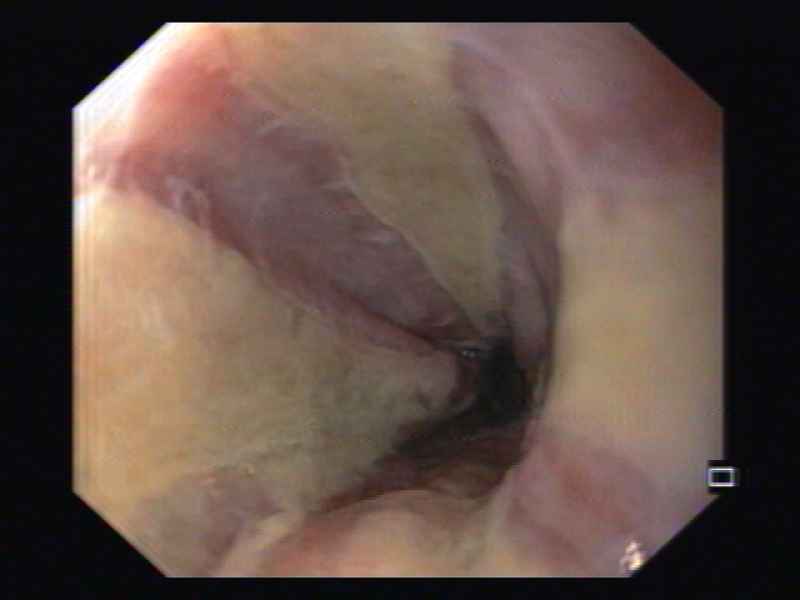

Bleeding oesophageal tear – an uncommon presentation

Fotografia